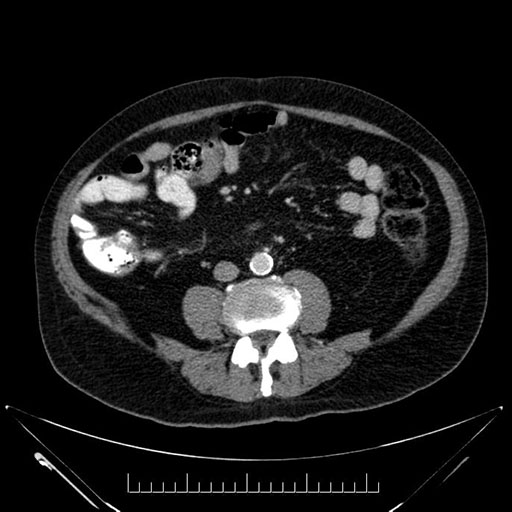

Imaging Analysis

Look through the patient's CT scan to identify any areas of concern for the necessary procedure.

Based on your CT findings, which issue(s) would give reason for "planned slowing down moment(s)" in this case?